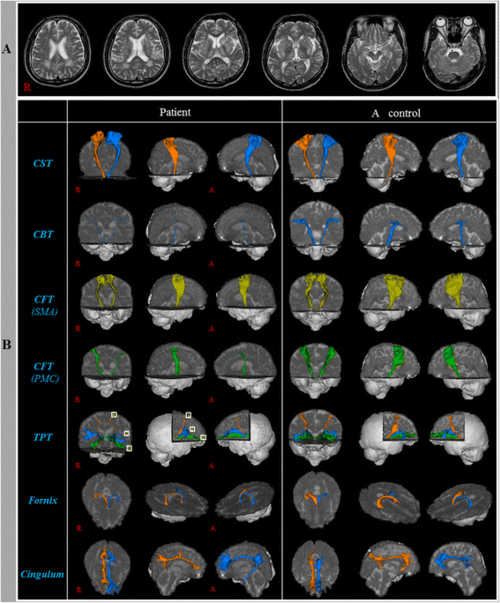

injuries of neural tracts in a patient with cadasil: a diffusion